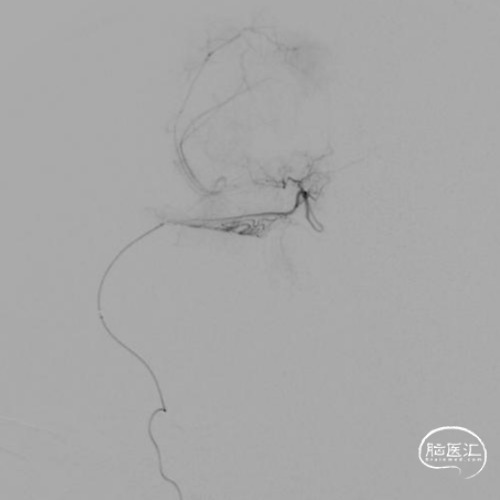

本例患儿肿瘤位于双侧额顶叶,大脑镰旁,增强扫描呈明显环形强化,提示肿瘤血运丰富。患儿年龄小,体重低,相对血容量少,如何控制术中出血是手术成功的关键。而术后肢体瘫痪或瘫痪加重是手术的主要并发症,中央沟静脉损伤、胼周动脉损伤、中央沟局部皮层损伤、癫痫、血肿以及脑水肿加重是其常见原因。术前脑血管造影有助于判断肿瘤与周围血管、组织的位置关系,明确上失状窦有无闭塞,对手术的切口设计有重要的参考价值及避免术中损伤不易发现的血管及组织。

本例患者术前脑血管造影提示瘤体主要由双侧大脑前动脉终末分支供血,造影静脉期瘤体显影明显,因此我们选择先采用神经介入技术超选部分主要供瘤动脉予弹簧圈栓塞,减少瘤体的供血。之后再行开颅探查双侧额顶叶占位性病变切除术。